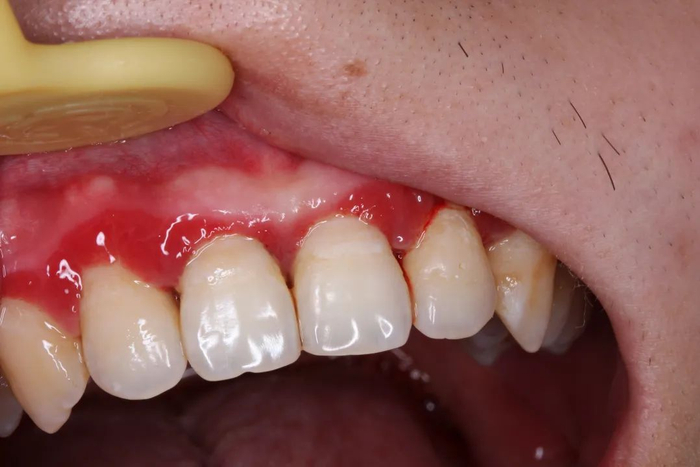

一开始出现的症状大概率是:牙龈有点发红、刷牙的时候有点出血,或者啃一口苹果后发现留下了一圈血印子。

刚开始,仅仅是出现牙龈红肿及出血,并不一定导致疼痛,图源:作者提供